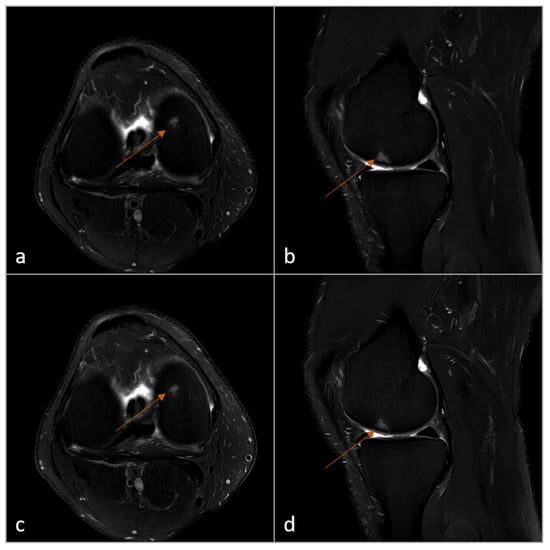

2.4. Subjective Image Analysis

3.3. Subjective Image Analysis

3.4. Objective Image Analysis